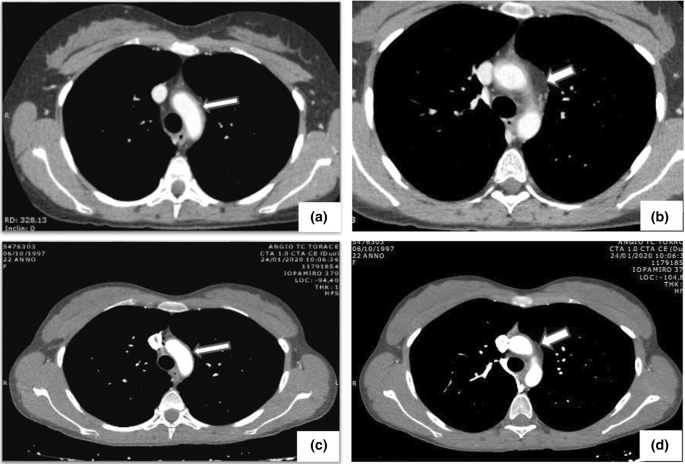

Computed tomography angiography (CTA) was performed in all patients and provided a clear image of the vessels involved as well as the lumen abnormalities, including stenotic and aneurysmal lesions (Figs. 2 and 3). Based on the angiographic patterns, the disease in each patient was classified according to the five above-described types (Fig. 4). Types I and V were the most common, diagnosed in 25.6% and 20.9% of the patients, respectively, followed by type IIa (18.6%), type IIb (13.9%), type IV (11.6%), and type III (9.3%). The limitations of CTA are the use of iodinated contrast agent, administered intravenously, and the exposure of patients to a high level of radiation.

Fig. 2

figure 2

a, b Angio-CT with intravenous iodinated contrast medium: note the circumferential thickening and enhancement of the aortic arch wall (arrows). c, d Following medical treatment and using the same sequence scans, both wall thickening and enhancement are clearly reduced